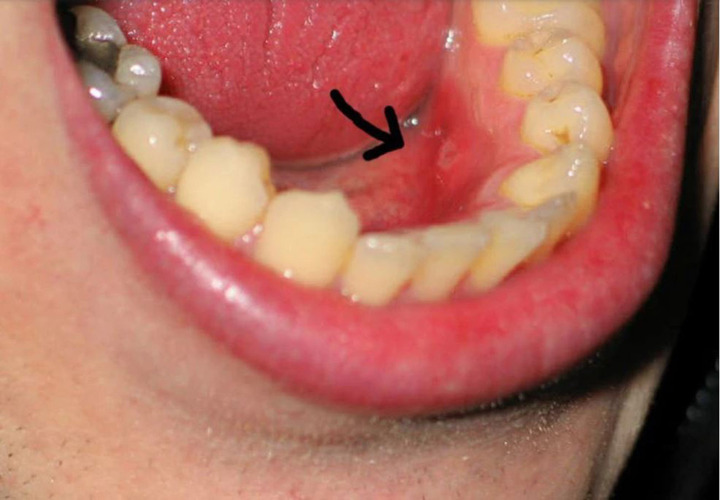

Ung thư khoang miệng triệu chứng dễ nhầm với nhiệt miệng (Ảnh minh họa)

Một số triệu chứng dễ gặp nhưng dễ bị nhầm lẫn với nhiệt miệng gồm: Vết loét trong miệng kéo dài; mảng trắng hoặc đỏ bất thường trên niêm mạc miệng, lưỡi hoặc lợi; Đau âm ỉ hoặc rát nhẹ ở lưỡi, lợi, má trong; Chảy máu nhẹ không rõ nguyên nhân khi đánh răng hoặc ăn uống.

Khi bệnh tiến triển hơn, các dấu hiệu có thể rõ ràng hơn như: Khó nhai, khó nuốt, nói khó; Đau lan lên tai hoặc vùng hàm; Nổi hạch ở cổ; Sụt cân không rõ nguyên nhân.

Các bác sĩ lưu ý, điểm quan trọng nhất để phân biệt với bệnh lành tính là tính chất kéo dài và không đáp ứng với điều trị thông thường. Vì vậy, bất kỳ tổn thương nào trong khoang miệng tồn tại quá 2 - 3 tuần đều cần được kiểm tra chuyên khoa càng sớm càng tốt.